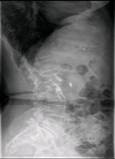

术前MRI检查